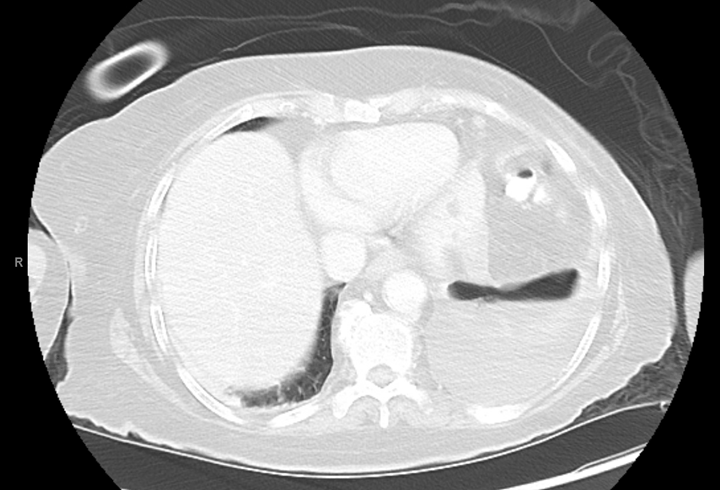

The family presented to our emergency department the same day of discharge, as the patient had not been eating and the family needed assistance in using the G tube. In-house computed tomography (CT) of the abdomen/pelvis again showed an organizing collection near the spleen (Image 1). A medium-sized left pleural effusion with left lower lobe collapse due to the communication with the perforation was observed on CT. The patient received IV fluids and a dose of vancomycin and zosyn in the ED. A vascular and interventional radiology (VIR) consult was recommended for potential drainage of the perisplenic abscess and left pleural effusion.